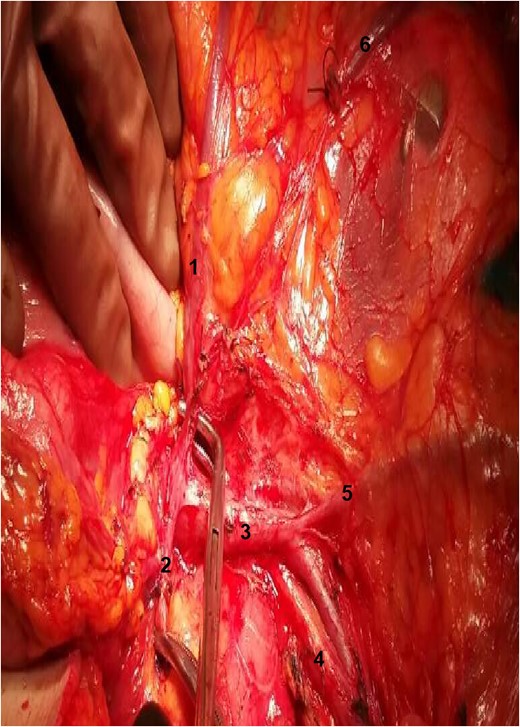

Exposure of the operative field. 1: RCA; 2: gastroepiploic artery; 3: superior mesenteric vein; 4: SMA; 5: ileocolic vein; 6: stump of right colic vein.

The relation between the vessels: 1: gastroepiploic artery; 2: RCA; 3: superior mesenteric vein; 4: SMA.

During the operation, surgeons attained to isolate the main supplying arteries of the right colon and their origins. The ileocolic and the middle colic arteries were observed, as typically, emerging as isolated vessels from the superior mesenteric artery (SMA). However, the origin of the RCA was nor observed from the SMA, nor from the previous arterial branches, as in common. Surgeons continued ascending dissection in order to detect the origin of the RCA that was finally observed arising from the right gastroepiploic artery (Figs 1–2). Pericolic lymph nodes and the lymph nodes that followed the central wards of the ileocolic, the middle colic and the aberrant RCA were gently dissected. The operation continued in the usual pattern. A drainage was placed and was finally removed the 6th postoperative day. The patient was discharged the 10th postoperative day with instructions. At the follow-up, the 14th postoperative day, the patient suffered no complications whatsoever.